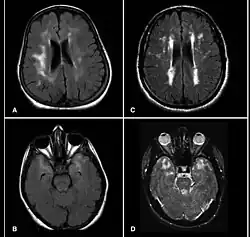

Bildgebende Verfahren

In der Magnetresonanztomographie des Gehirns finden sich in T2-gewichteten Aufnahmen Signalverstärkungen in der weißen Substanz, typischerweise insbesondere auch temporal.